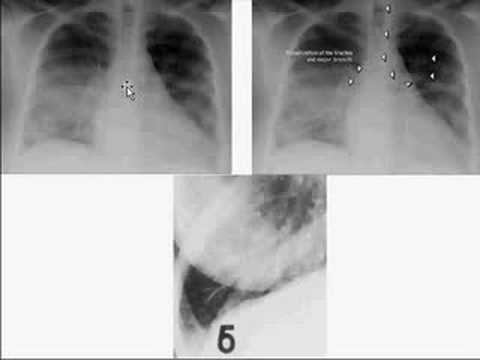

Medical School Pathology, Chapter 4c